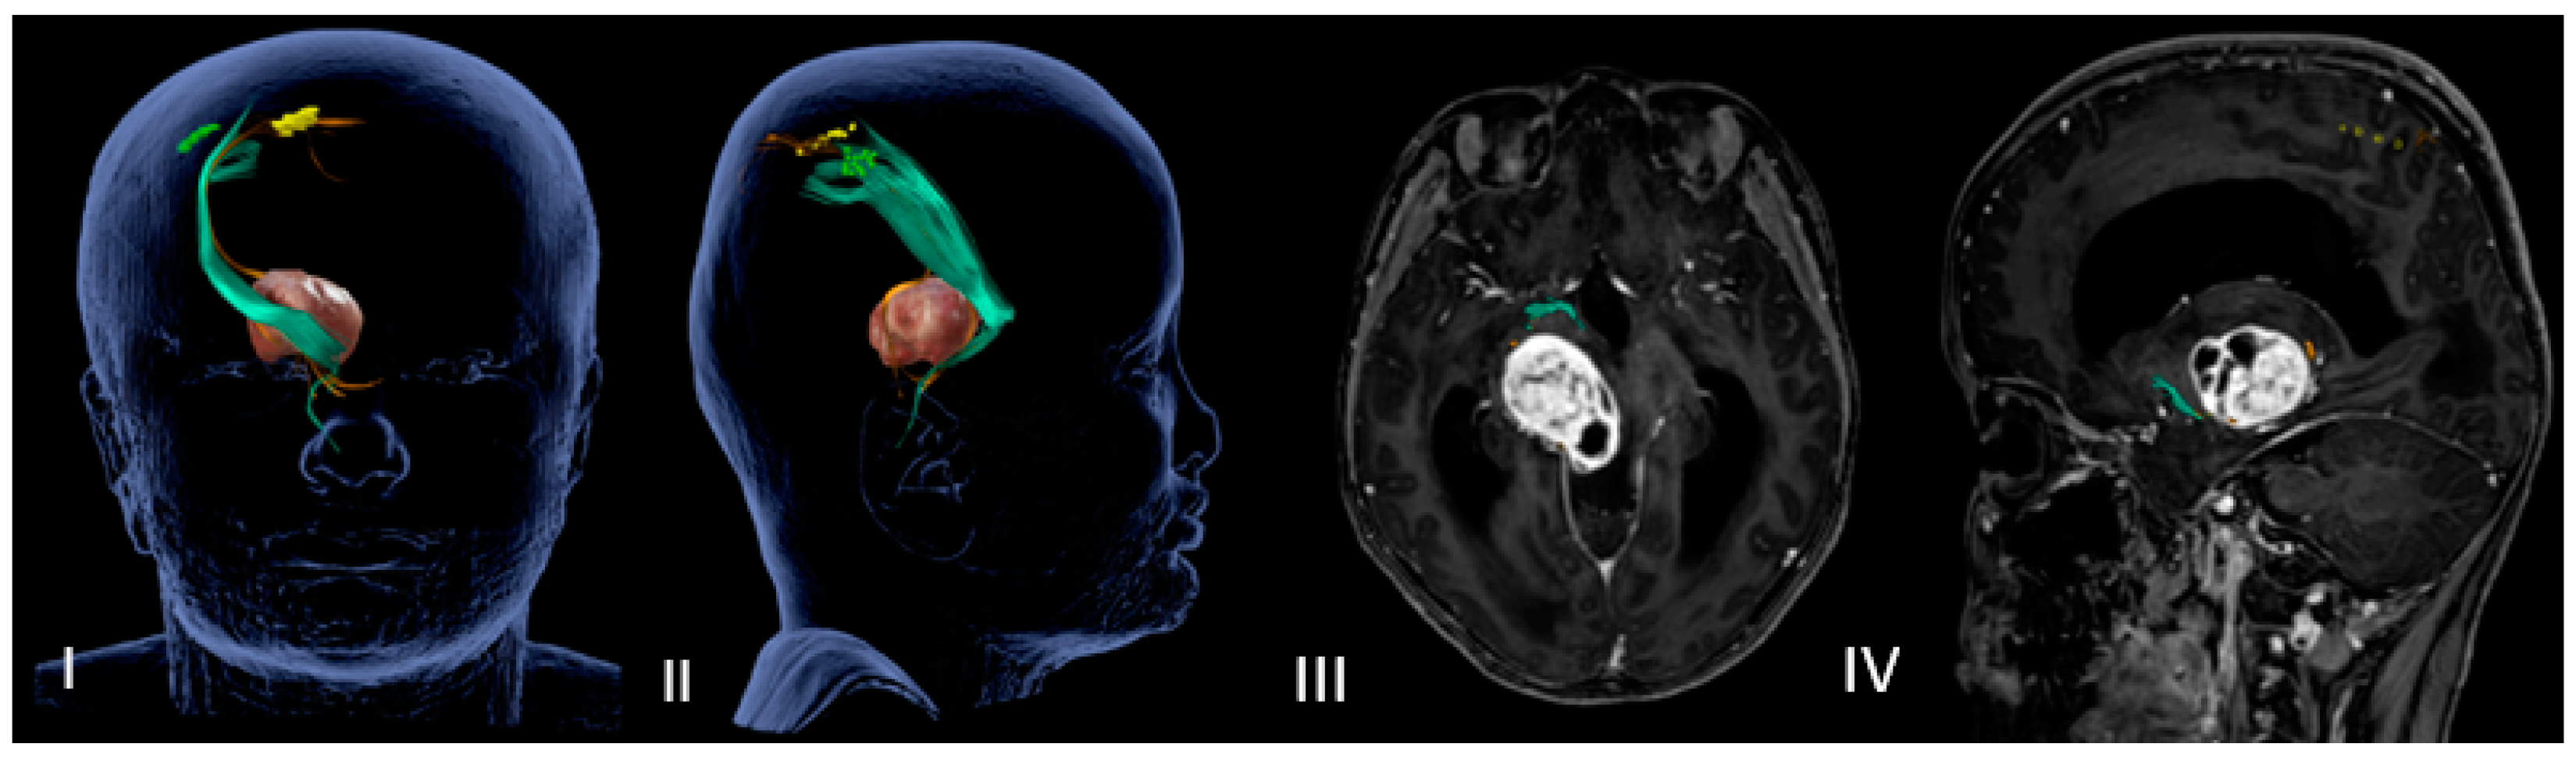

Figure 2.

Neuronavigated transcranial magnetic stimulation pre-op study. (I,II) A 3D reconstruction of the nTMS data that shows cortical maps of the right spinal tract (CST) for the foot (blue) and hand (orange) and its relationship with the thalamopeduncular tumor of Case A. (III,IV) Brain MRI merged with nTMS data showing that the cortical spinal tract (CST) runs antero-medially respect to a right thalamopeduncular tumor.